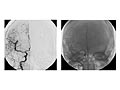

Angiogram of the Head and Neck

An angiogram of the head and neck is an X-ray test that uses a special dye and camera (fluoroscopy) to take pictures of the blood flow in the blood vessels of the head and neck. An angiogram of the neck (carotid angiogram) can be used to look at the large arteries in the neck that lead to the brain. An angiogram of the head (cerebral angiogram) can be used to look at the veins or the four arteries (four-vessel study) carrying blood to the brain.

An angiogram can find a bulge in a blood vessel (aneurysm). It can also show narrowing or a blockage in a blood vessel that slows or stops blood flow. An abnormal pattern of blood vessels (arteriovenous [AV] malformation) or abnormal vessels near a tumor can be seen.

Normal:

The blood vessels are normal in size, shape, location, and number.

The dye flows evenly through the blood vessels.

No narrowing, blockage, bulging, or other problem of the blood vessels is seen.

Abnormal:

A narrow spot in an artery may mean that a fat deposit, calcium deposit, or clot is reducing blood flow through the blood vessel.

Blood vessels that are not in their normal position may mean that a tumor or other growth is pushing against them.

A bulge in a blood vessel may point to a weakness in the blood vessel wall (aneurysm).

An abnormal pattern of blood vessels may mean that a tumor is present.

Dye that leaks out of a blood vessel may mean that there is a hole in the blood vessel.

There is abnormal branching of blood vessels present since birth (congenital).